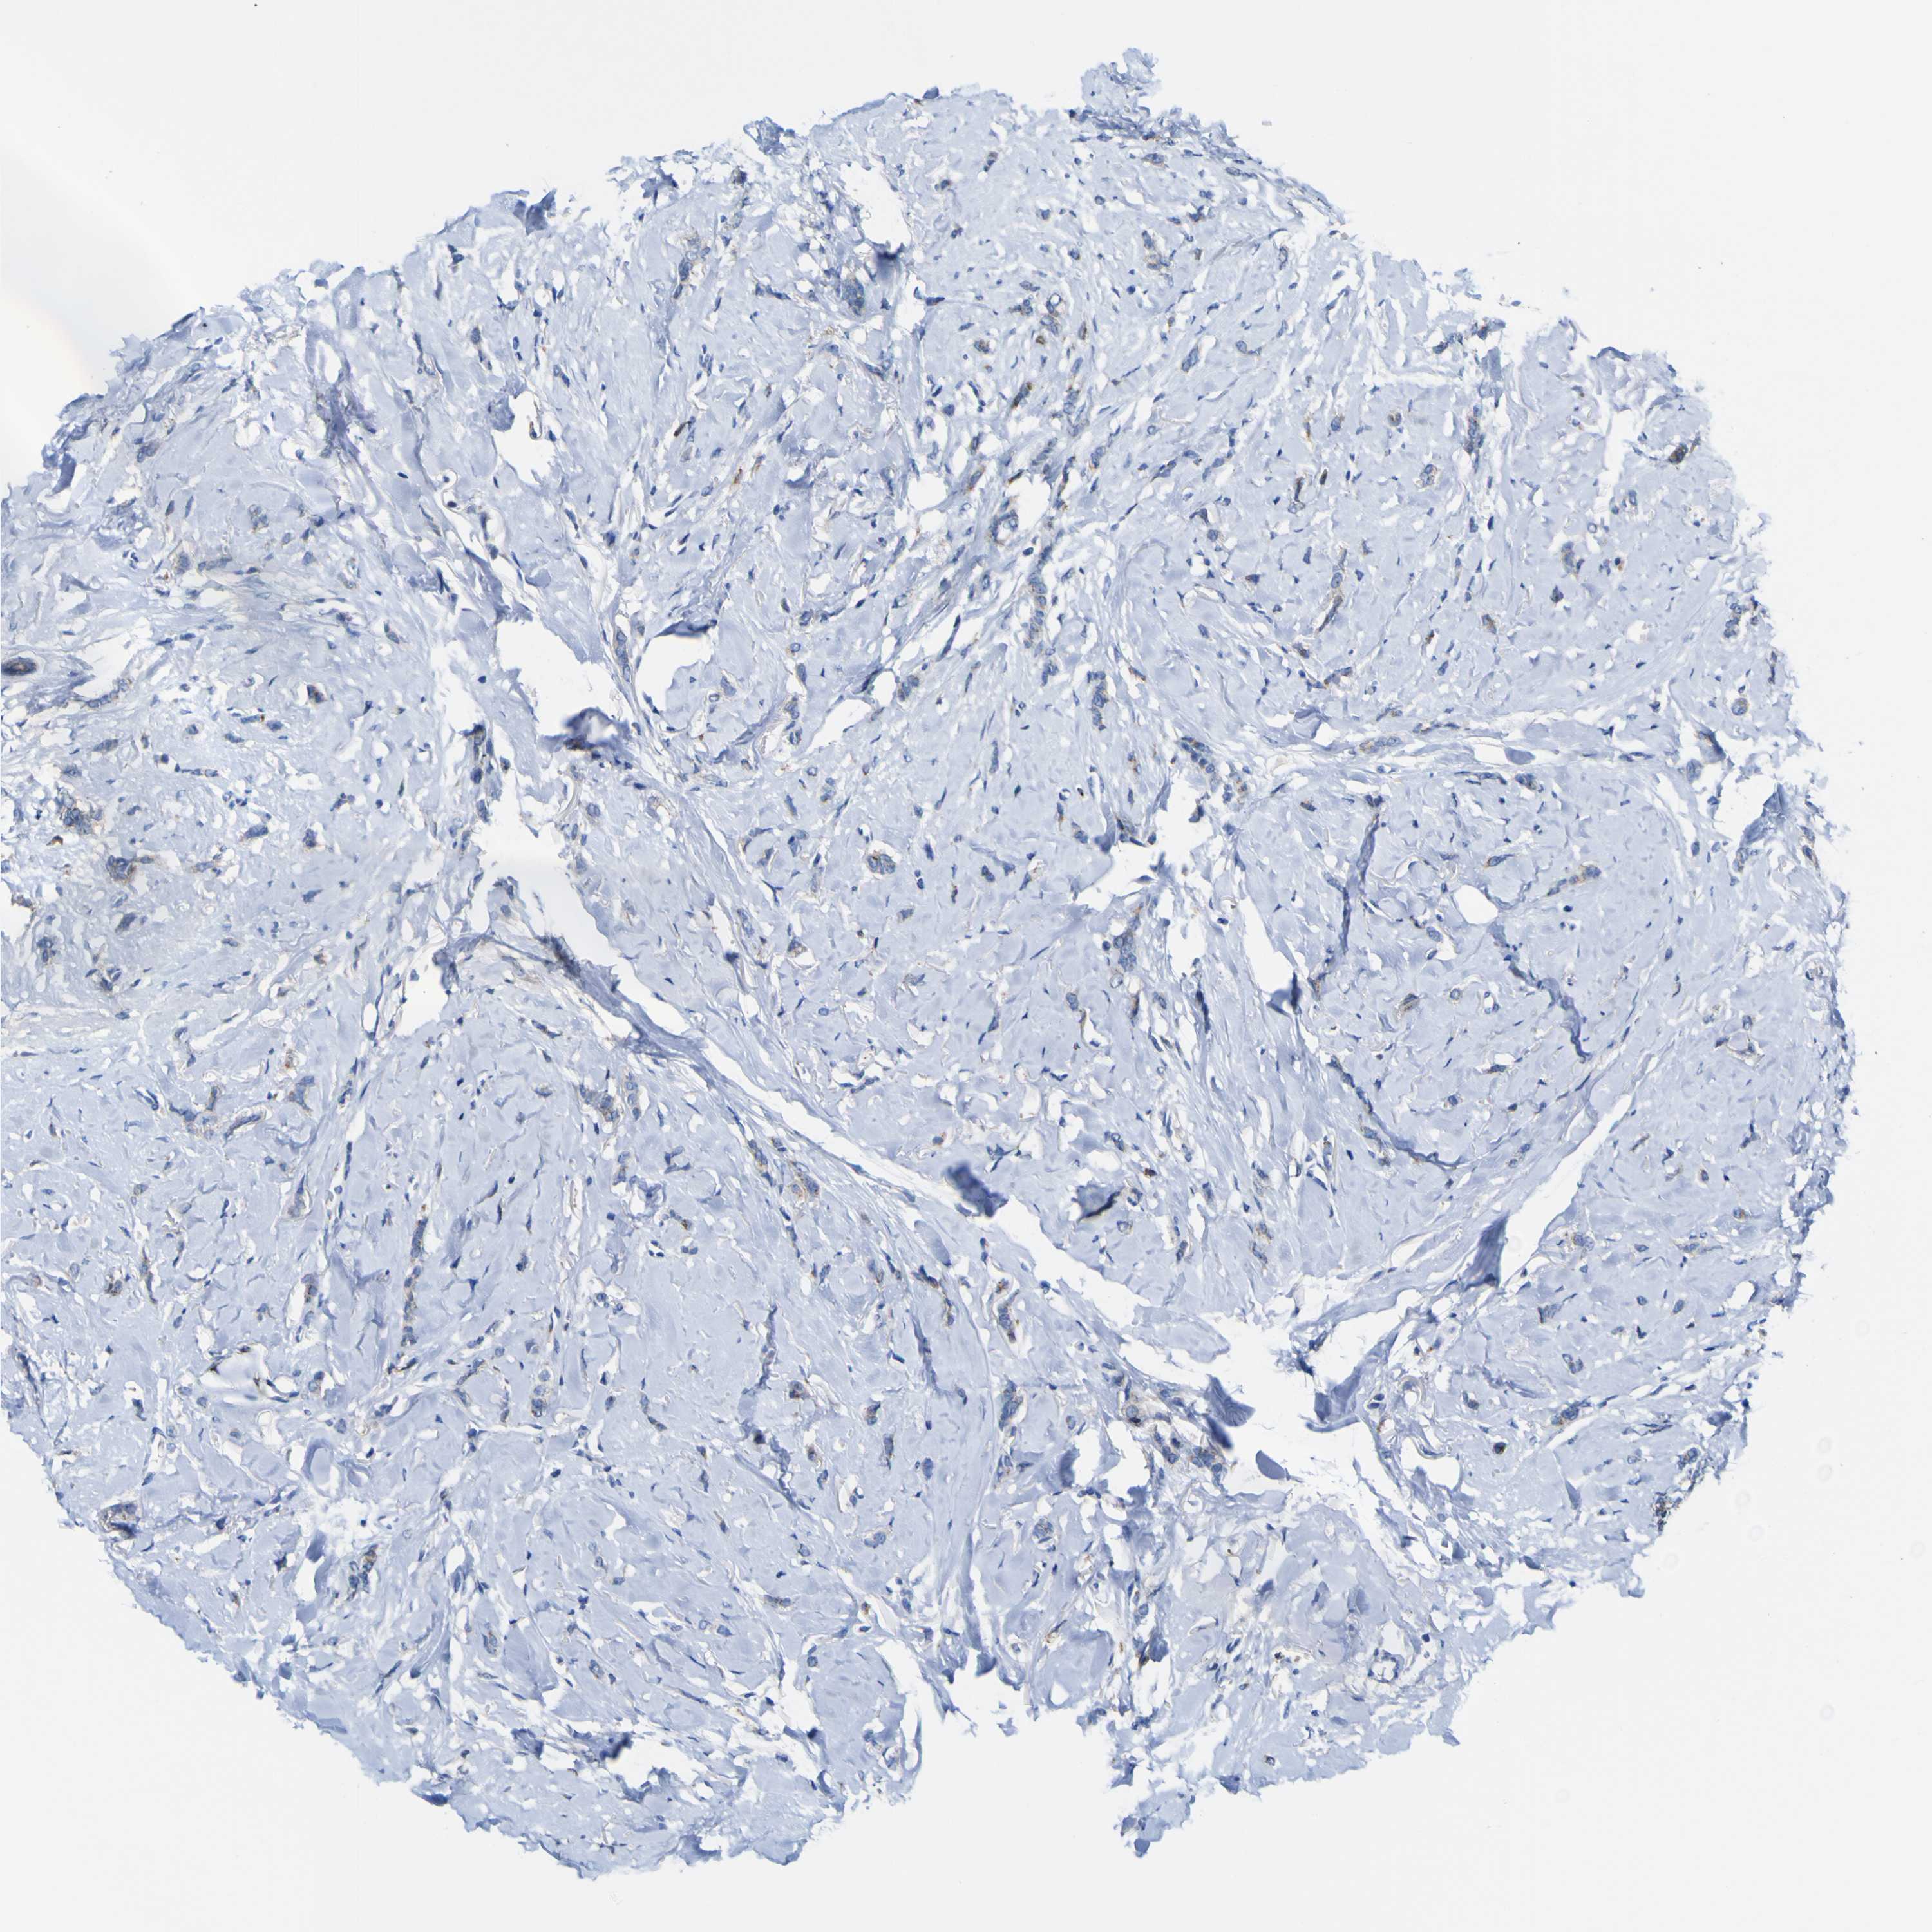

CANCER BREAST CANCER Show tissue menu

BRCA TCGA BRCA VALIDATION PROTEIN EXPRESSION